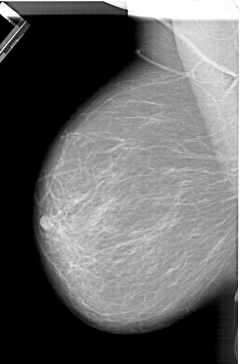

A_1333_1.RIGHT_MLO

RIGHT_MLO LINES 6451 PIXELS_PER_LINE 4306 BITS_PER_PIXEL 12 RESOLUTION 43.5 OVERLAY